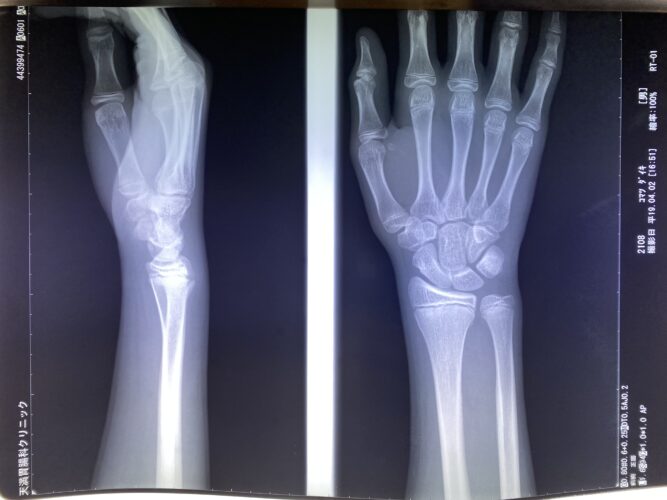

【橈骨遠位端骨折】コーレス骨折の治療とリハビリ|手術以外の選択肢と後遺症…